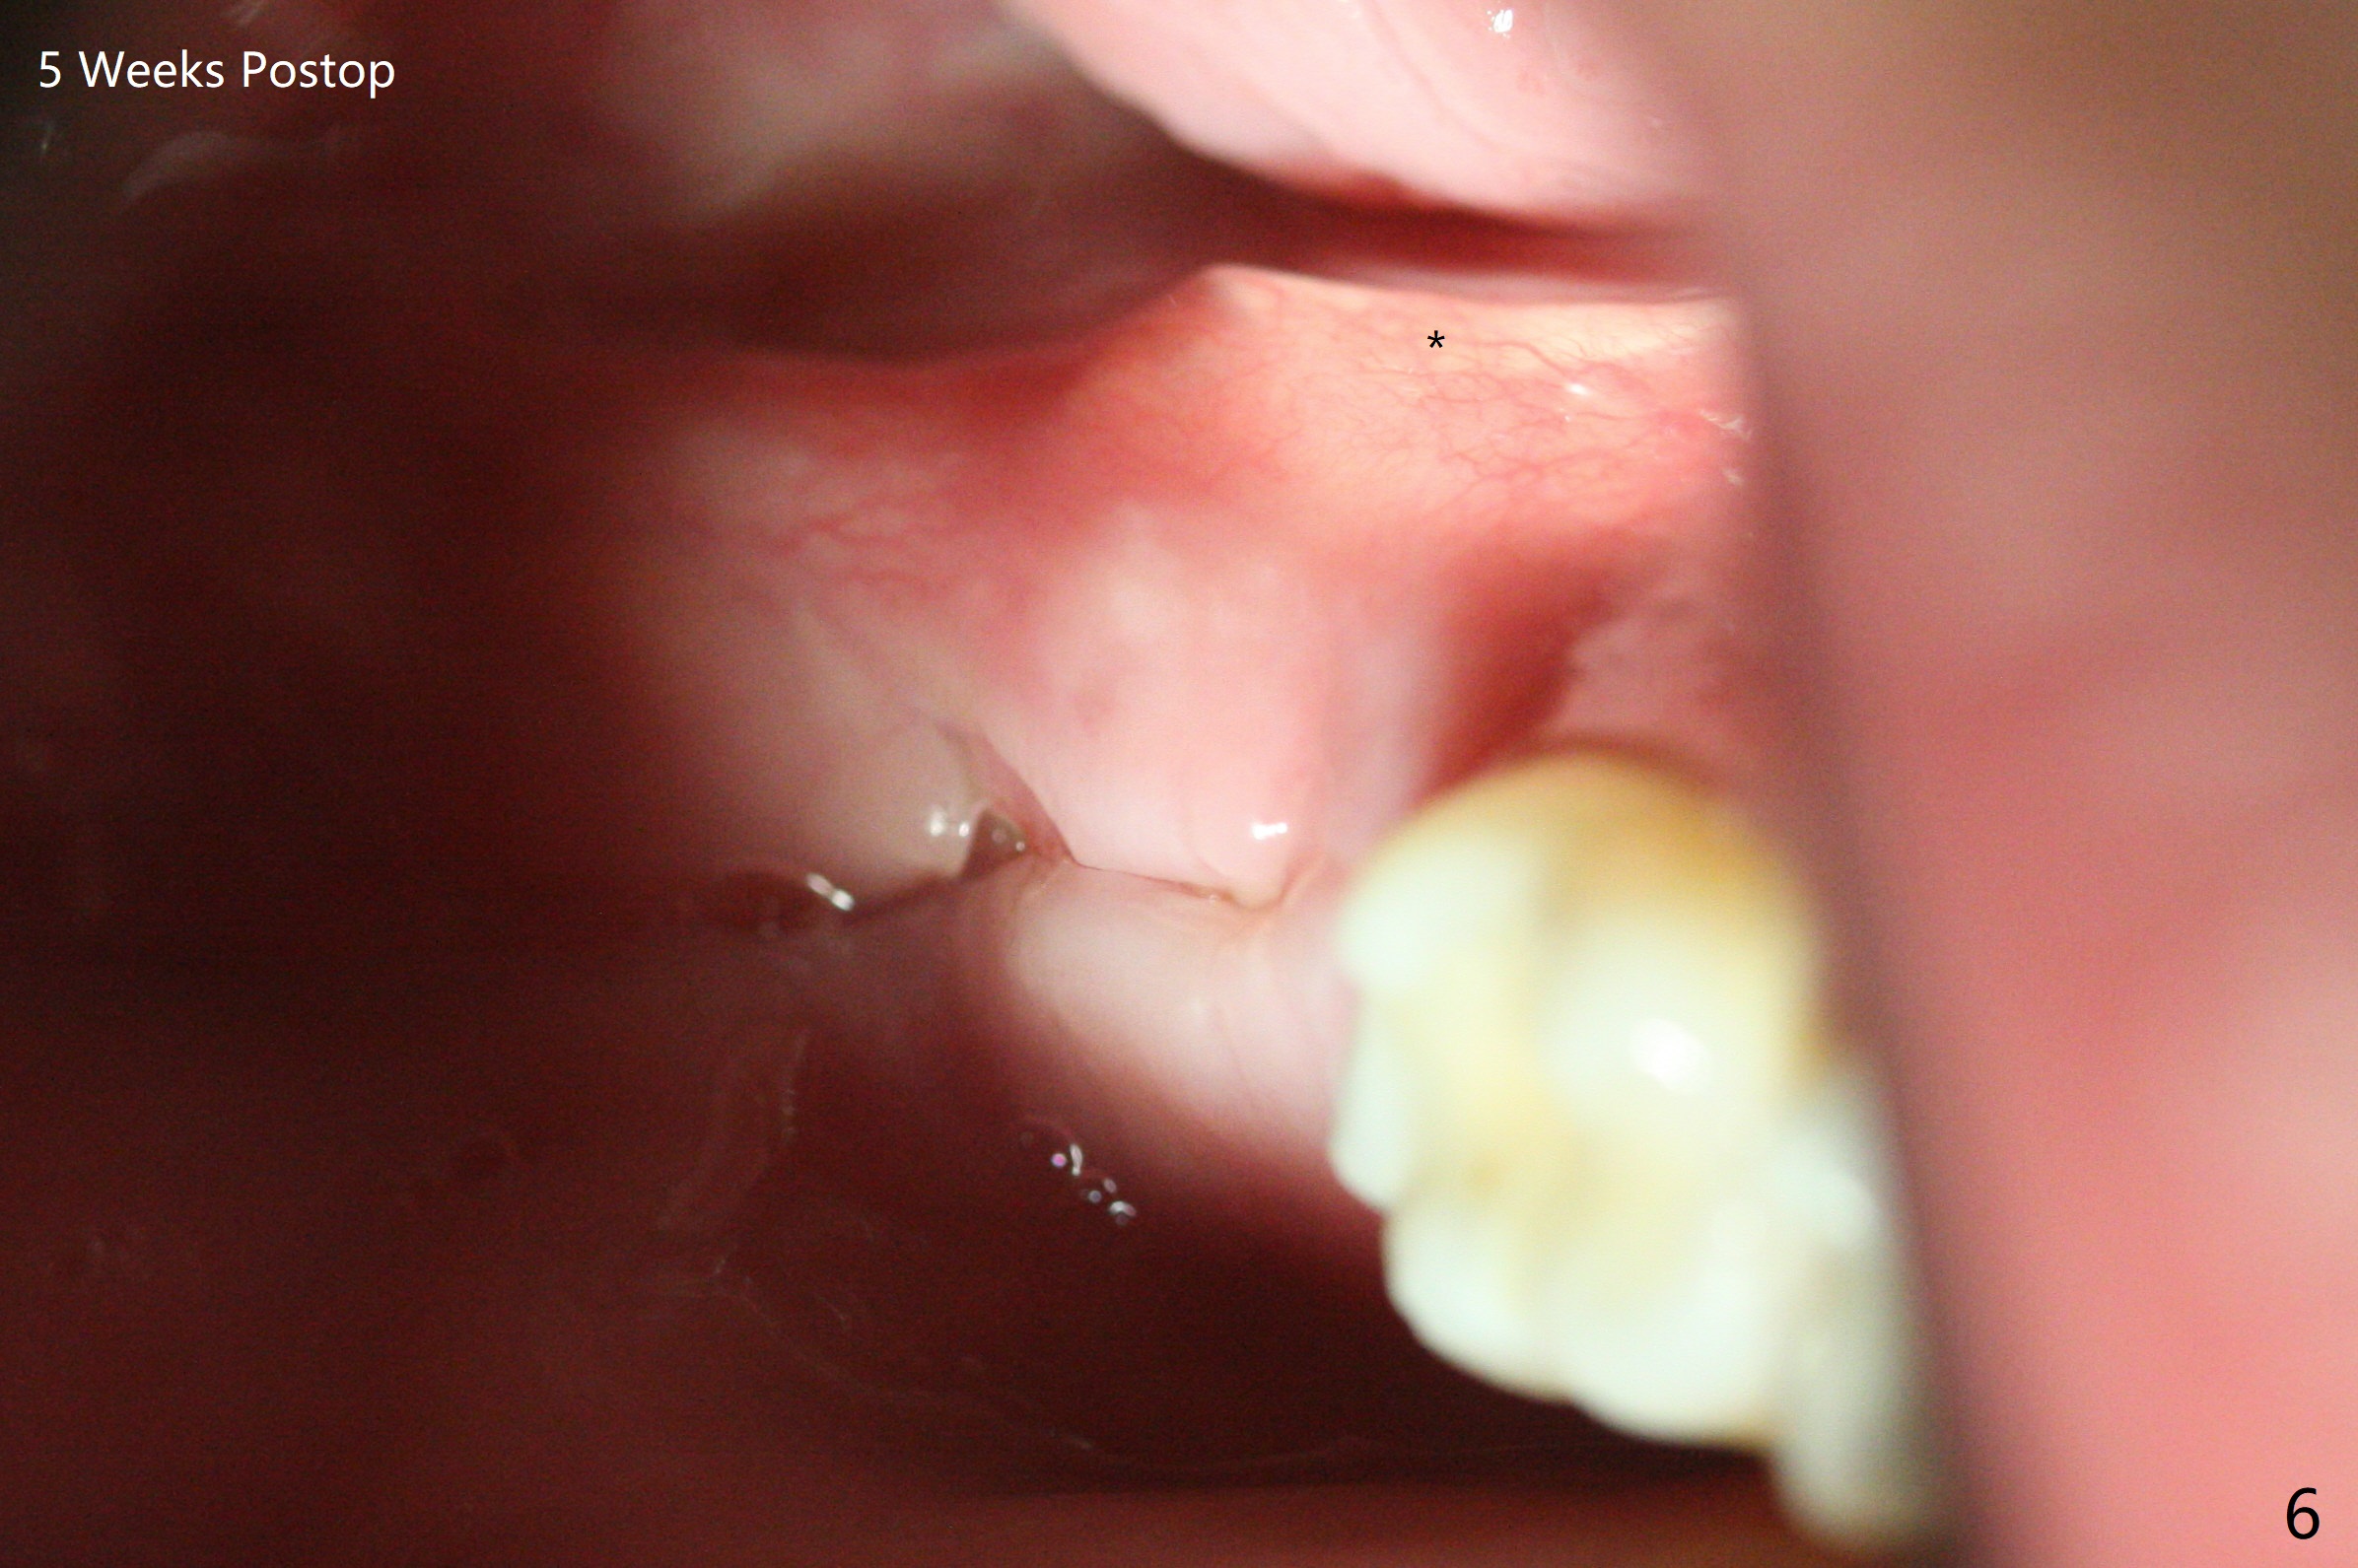

A 26-year-old man returns for #17,32 extraction 5.5 months post #1,16 one (Fig.1,2). In fact the crown/abutment at #31 is loose and removed, which makes easy for access, debridement with Titanium brush and bone graft (Fig.2 arrowheads, Ossogen). Osteogen plug is placed in the extraction sockets. The patient has limited mouth opening. Hemorrhage in #17 socket is controlled apparently with the plug following incomplete removal of granulation tissue. A piece of 12x12 mm Amnion-Chorion Membrane seems small for bone graft coverage. Cytoplast is added, followed by PGA suture. The former may keep the bone graft in place in case the wound dehisces. In fact the implant was not placed deep enough. It should have been removed. Although the wounds at #31/32 and 17 heal 7 days postop (Fig.3,5), the Cytoplast is visible immediately underneath the lingual gingiva at #31 (Fig.4 * (bulging)). The patient returns for Cytoplast (Fig.6 (occlusal view) *) removal 5 weeks postop. The procedure is done smoothly.